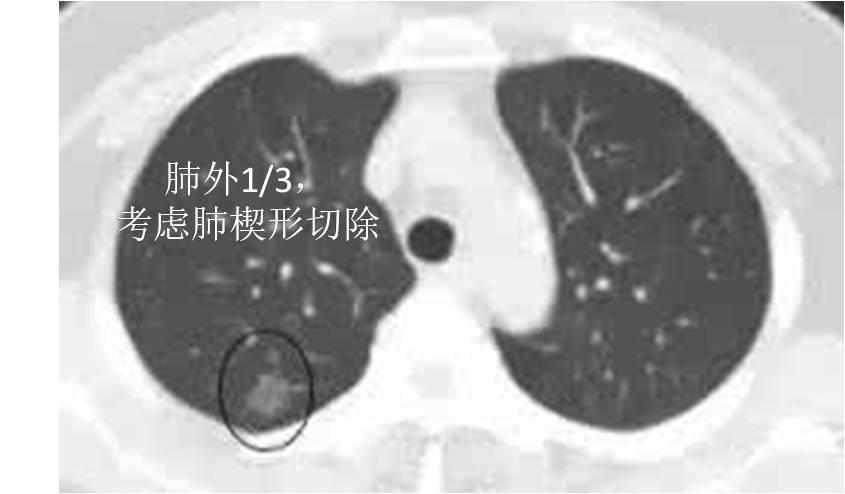

1. 肺组织按照从内到外大约分为内1/3,中1/3和外1/3三个区域。病灶位于肺组织1/3区域内,可以考虑行肺楔形切除术。病灶位于肺组织内1/3和中1/3区域内,可以考虑行肺段切除术或肺叶切除术。